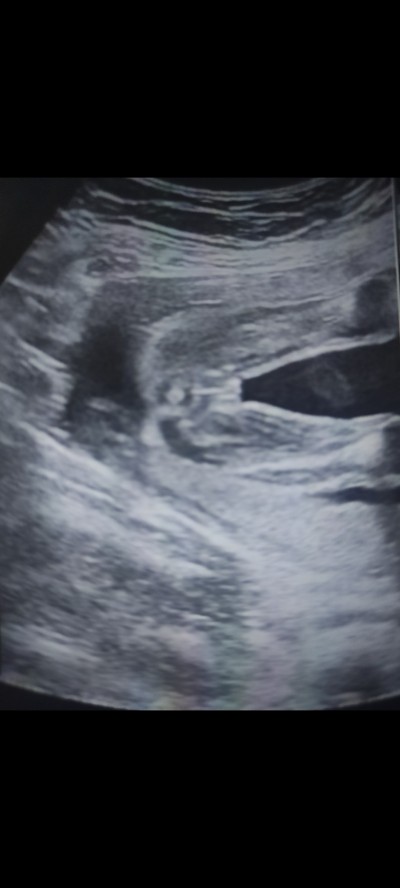

Kizlar cinsiyeti tahmin edebilir misiniz

Gebelik haftası 21

Canım çok net kız bebek

Kız olduğu çok belli

Kız bebek :)

Çok net kız